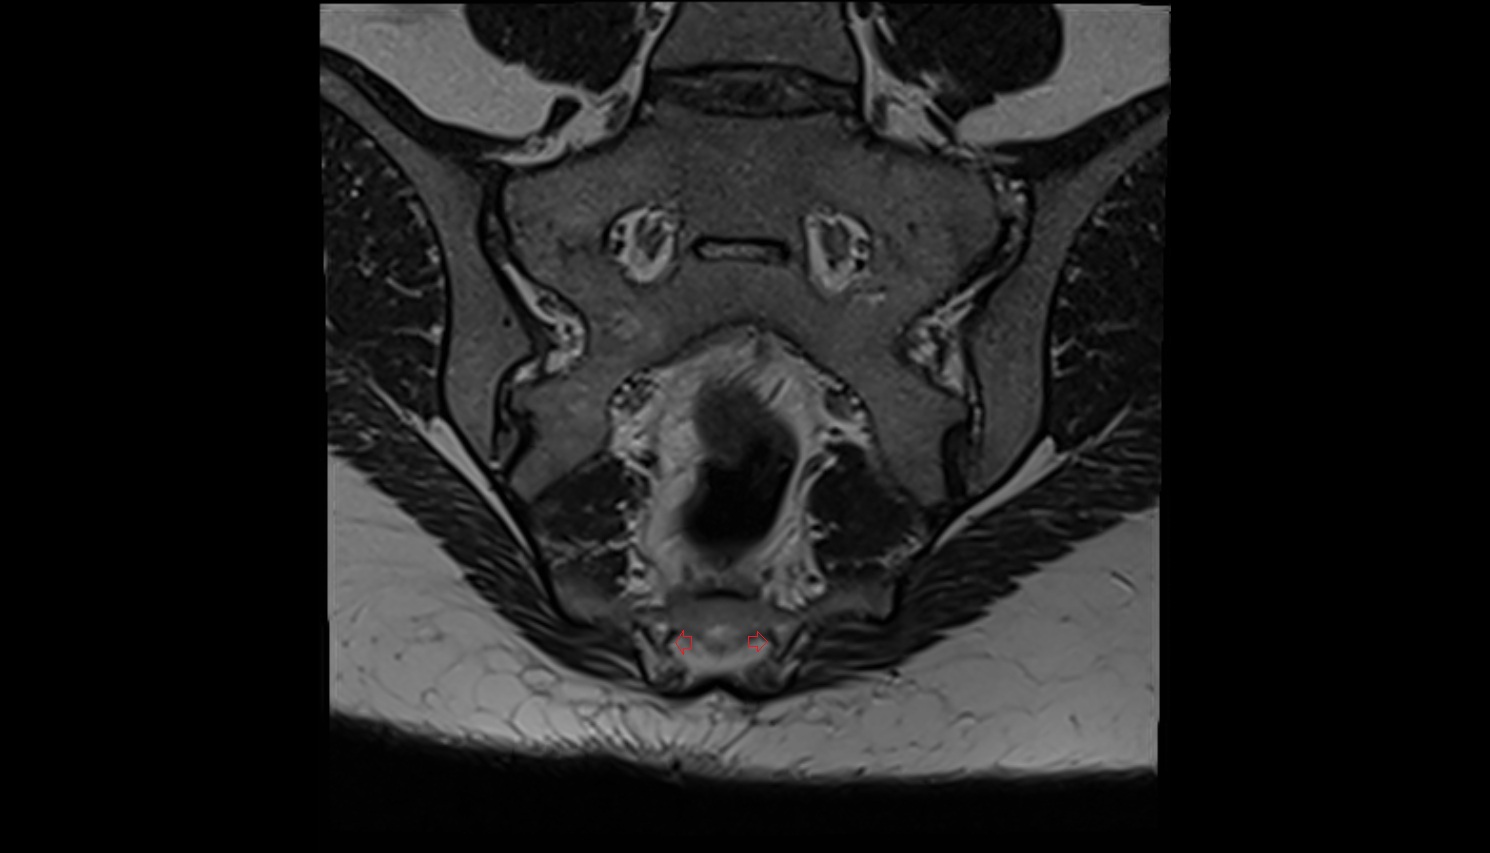

- Urinary bladder

- Uterus

- Cervix of uterus

- Vagina

- Pubic symphysis